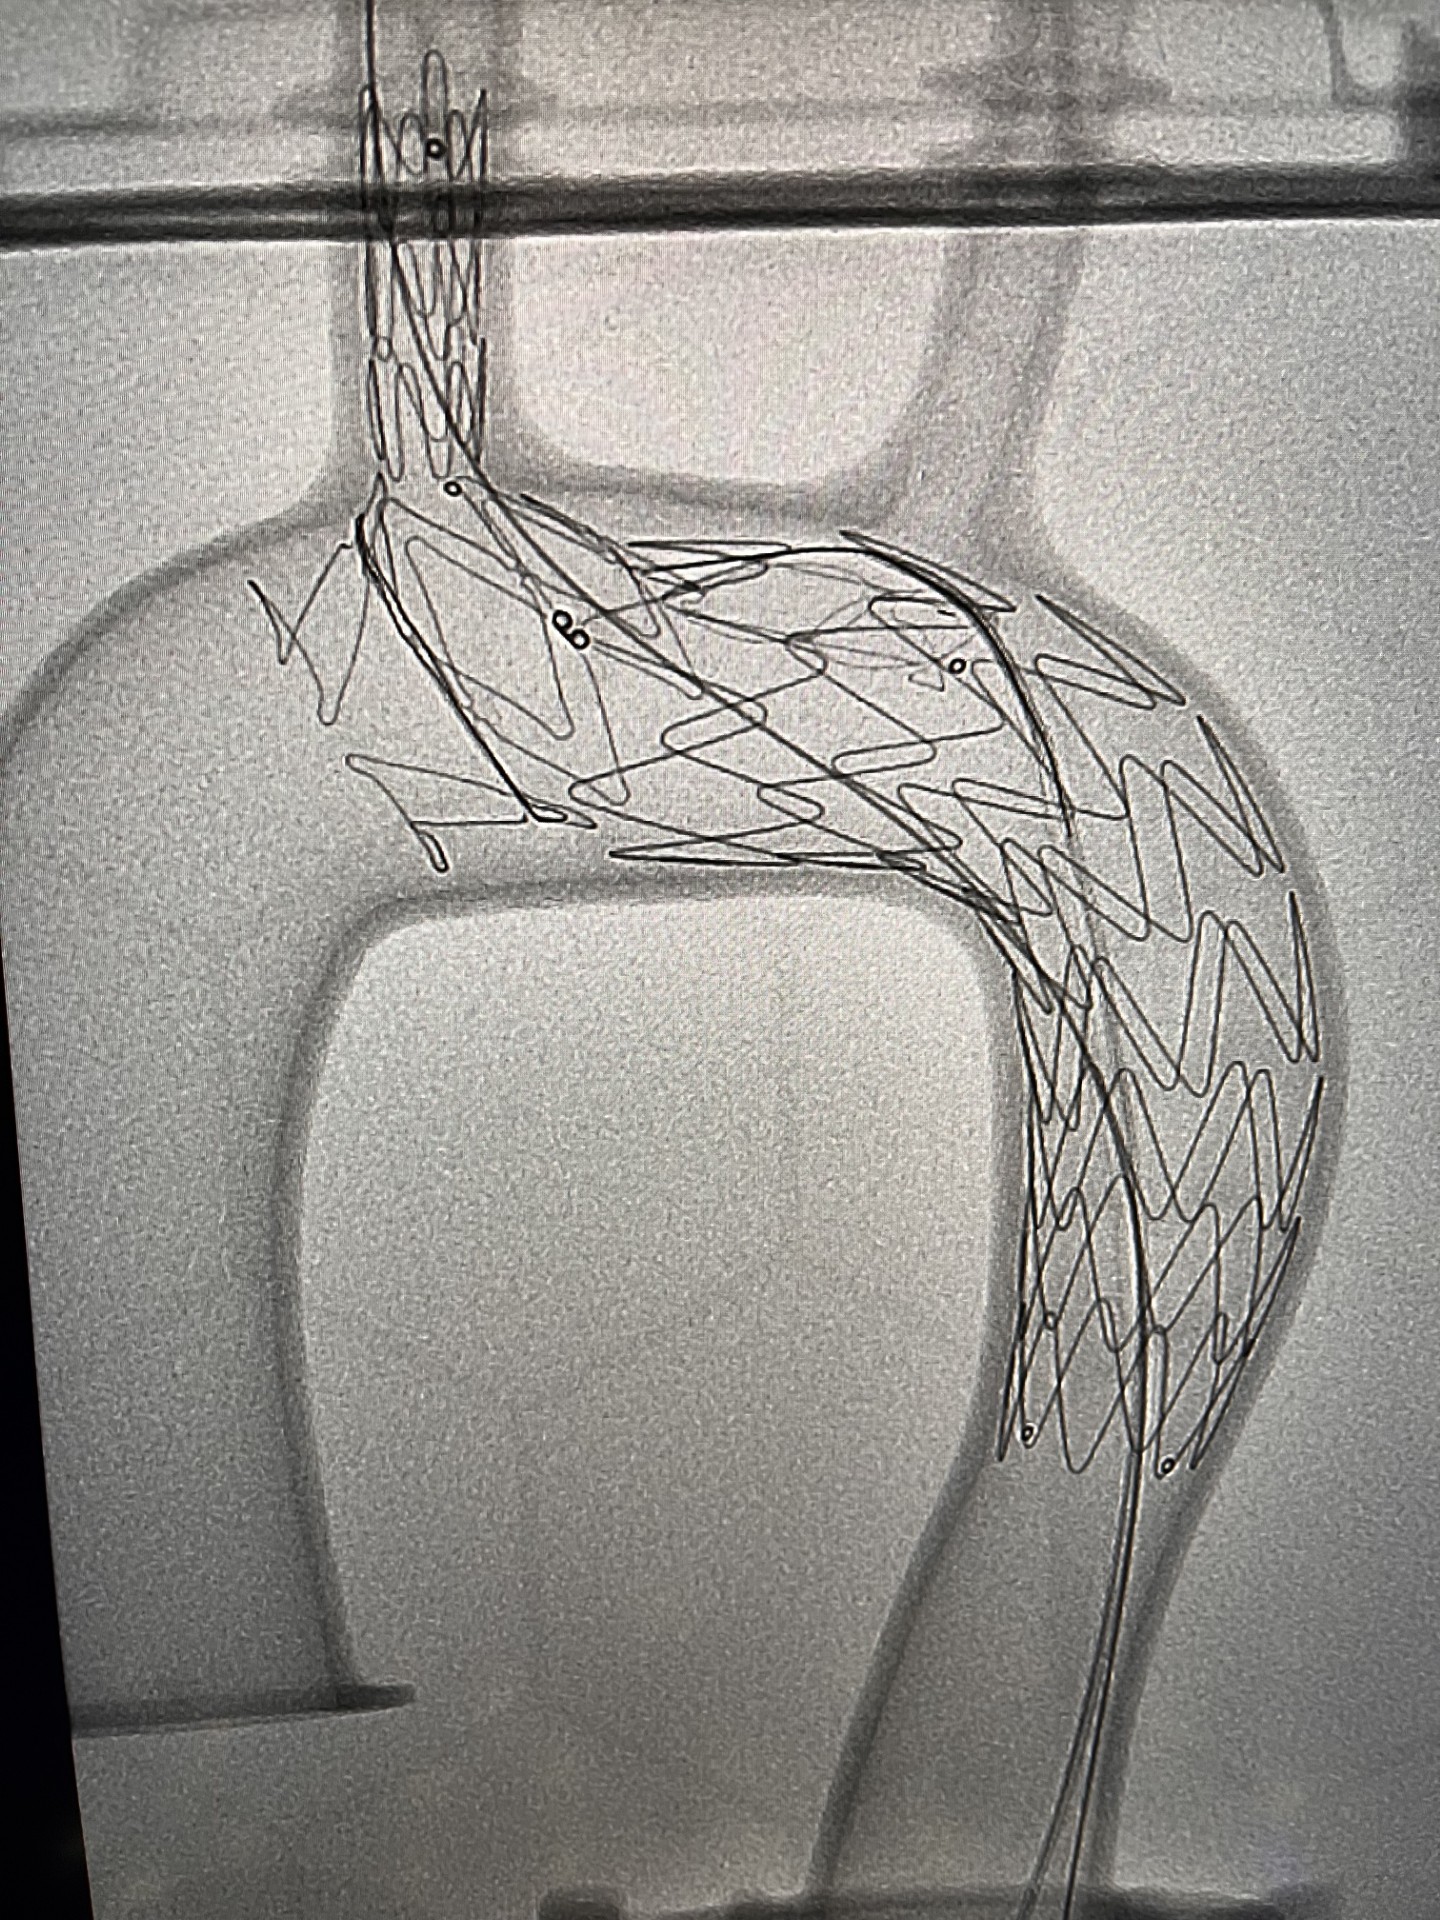

Pod koniec marca br. wykonano pierwszą w województwie pomorskim i trzecią w Polsce operację patologii łuku aorty systemem NEXUS TRE. Dzięki takiej procedurze udało się choremu uniknąć rozległej operacji kardiochirurgicznej z otwarciem klatki piersiowej oraz krążeniem pozaustrojowym.

Zespół chirurgów naczyniowych „Szpitali Pomorskich” rozpoczął w 2023 r. zabiegi endowaskularne w obrębie łuku aorty, dołączając tym samym do elitarnych oddziałów w Polsce. Obecnie ma na koncie liczne, wykonane z powodzeniem zabiegi.

Zabieg był dodatkowo wyjątkowy, gdyż chory obarczony jest niedrożnością obu tętnice szyjnych, odpowiedzialnych za dostarczanie krwi do mózgu. Czas zabiegu oraz zaangażowanie anestezjologa dr Pawła Dutki miał tu decydujące znaczenie — mówi doktor Ryszard Zając, ordynator Oddziału Chirurgii Naczyniowej Szpitala św. Wincentego a Paulo w Gdyni

Udaną operację przeprowadzono ze wsparciem specjalisty klinicznego, doktora Alana Abilio, który przyjechał z Brazylii. Chory bez powikłań udał się w piątej dobie do domu.